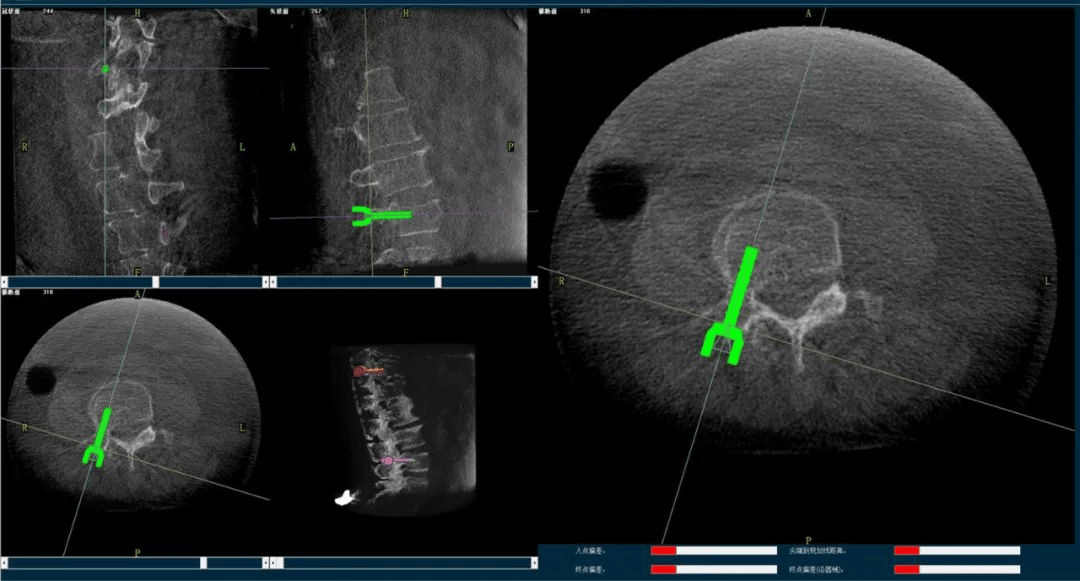

術(shù)中,手術(shù)團隊先對患者進行三維影像掃描,將圖像同步傳輸至機器人成像系統(tǒng)后,利用骨科手術(shù)機器人導(dǎo)航系統(tǒng)做好手術(shù)規(guī)劃,隨后利用其機械臂,將手術(shù)工具精確定位到“目的地”,鋪好“通道”,這就很好的解決了醫(yī)生“盲穿”的問題。

主任為患者注射骨水泥,再次影像掃描后,發(fā)現(xiàn)骨水泥進入位置非常好,彌散效果更佳,手術(shù)順利完成,患者的恢復(fù)也自然更好。